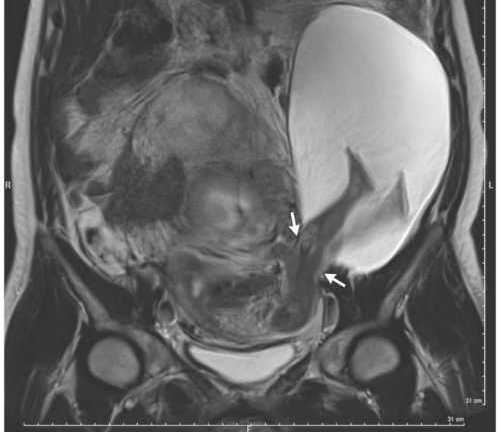

Hình ảnh siêu âm cho thấy, chân của thai nhi 22 tuần tuổi đạp rách và phát triển bên ngoài tử cung bà mẹ người Pháp.